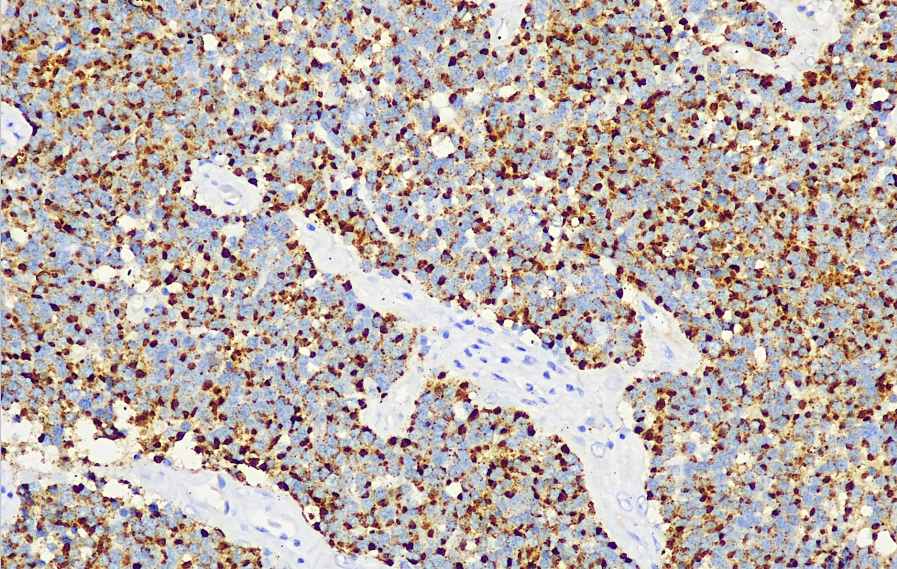

Cellular localization: cytoplasmic

Positive control: Pituitary gland

Prolactin is a hormone secreted by prolactin-producing cells in the acidophilic cells of the anterior pituitary gland. It promotes mammary gland development and milk secretion. This antibody reacts with human prolactin and is mainly used in research on the functional classification of pituitary tumors.

PRL antibody reagents can specifically bind to PRL molecular antigens. Immunohistochemistry kits containing PRL antibody reagents are suitable for the classification of pituitary tumors.